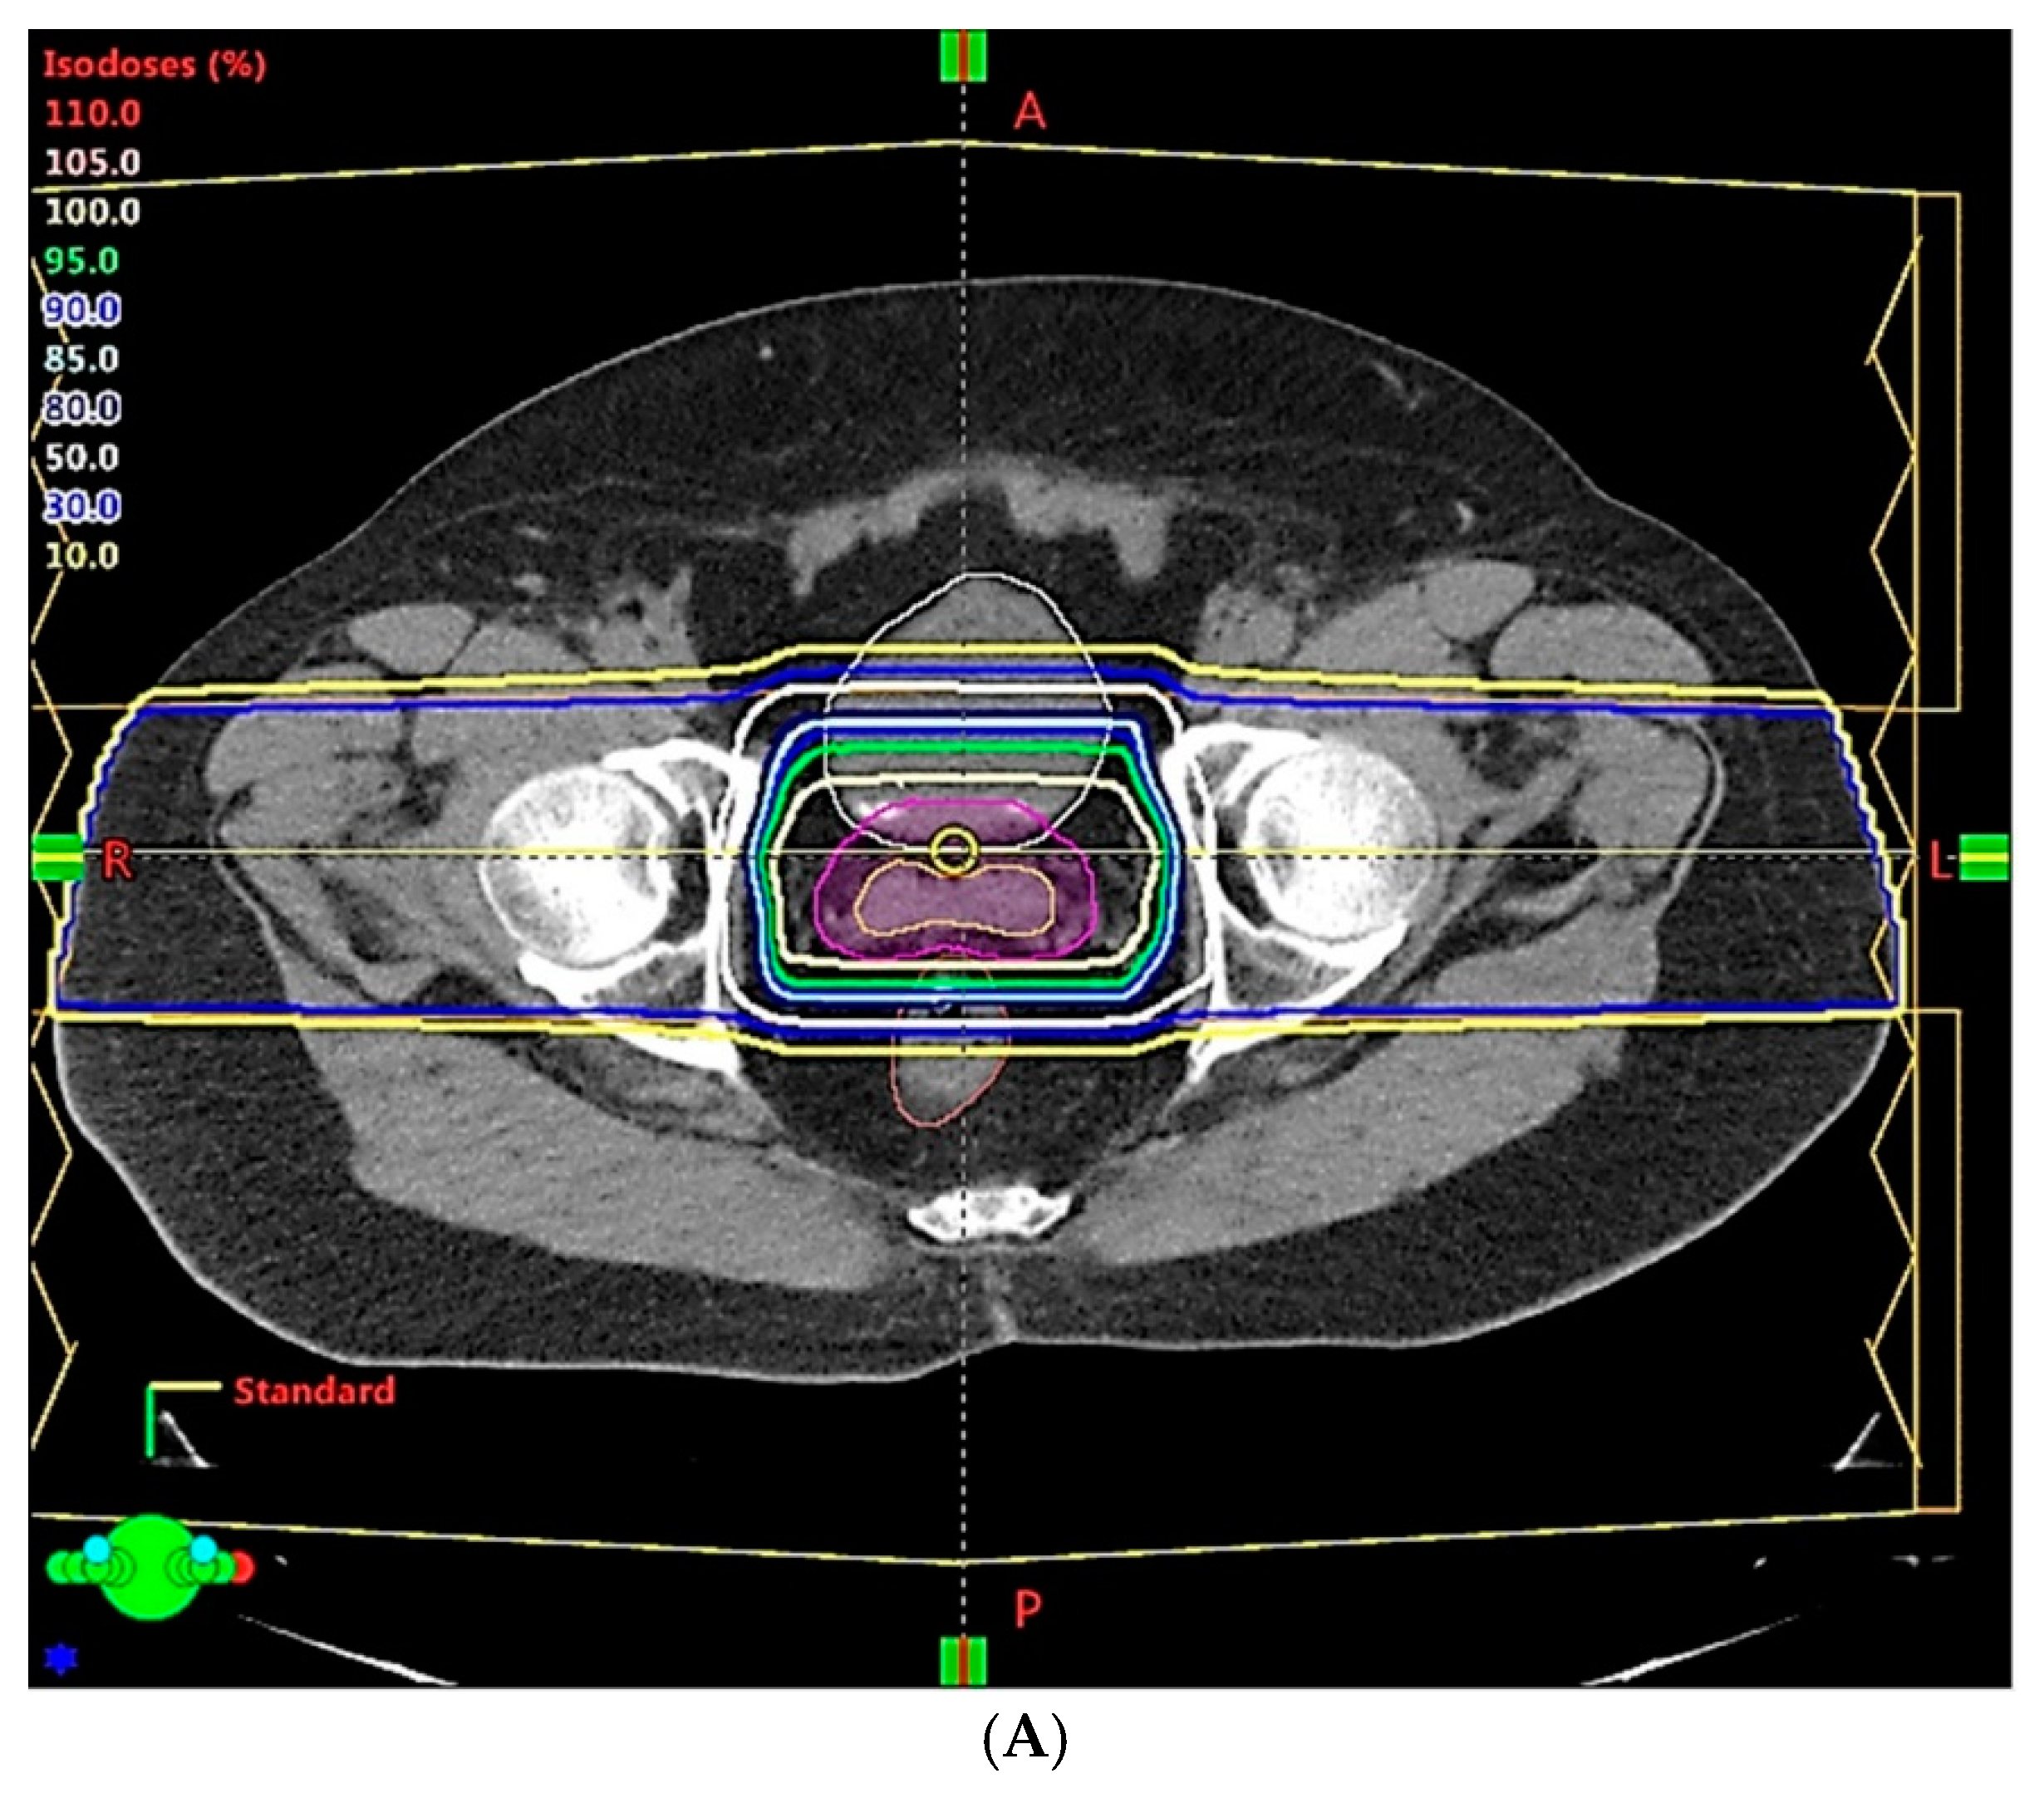

3. Opportunities for Improvement with New Technologies and Innovative Techniques